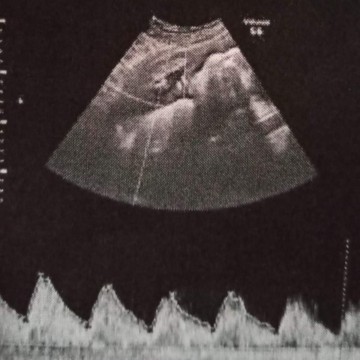

ตั้งครรภ์

อยากรู้ว่า แบบนี้ญ/ช คะ

ต้องซาวด์ให้เห็นระหว่างขาค่ะ